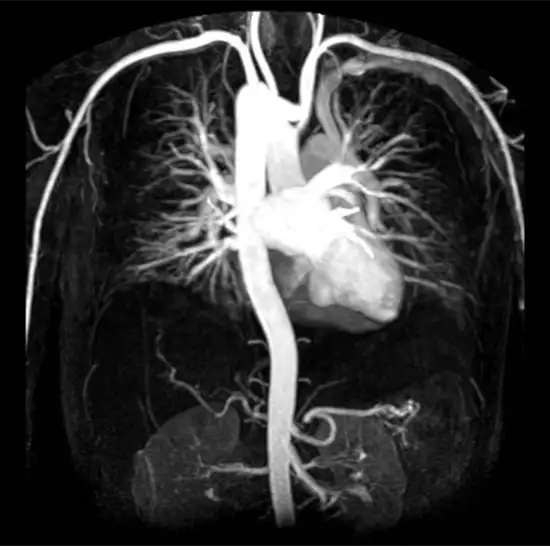

mr angiography chest scan

MR Angiography Chest

The MR Angiography Chest helps the doctor to check the blood vessels, arteries, and veins in your chest area to treat the abnormalities on time.

The MR Angiography Chest is done by using a fluoroscopy x-ray to substitute catheters in the blood vessels and injecting contrast to get clear images. Then use a magnetic field and radio waves to get the detailed structure inside the chest.